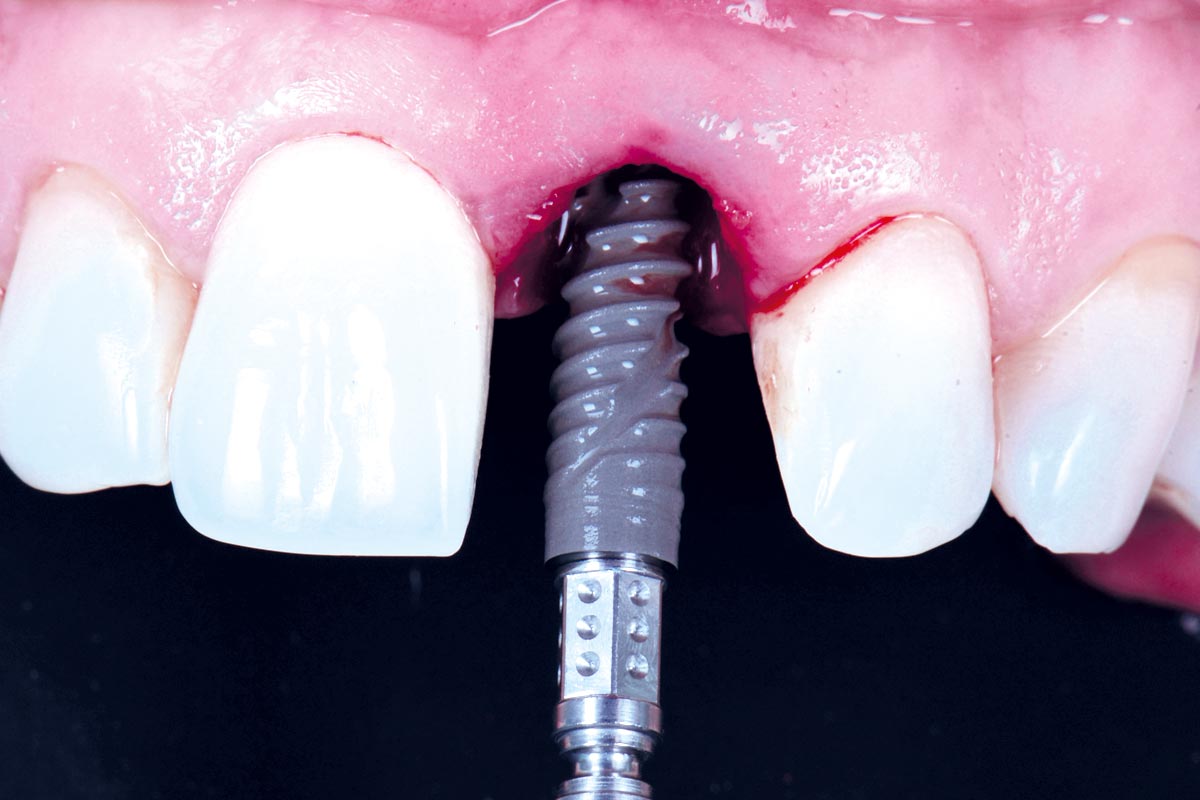

cerabone® and mucoderm® for immediate implantation in the aesthetic area - Dr. D. Robles

Initial clinical situation - Central incisors with dental destruction and periapical pathology